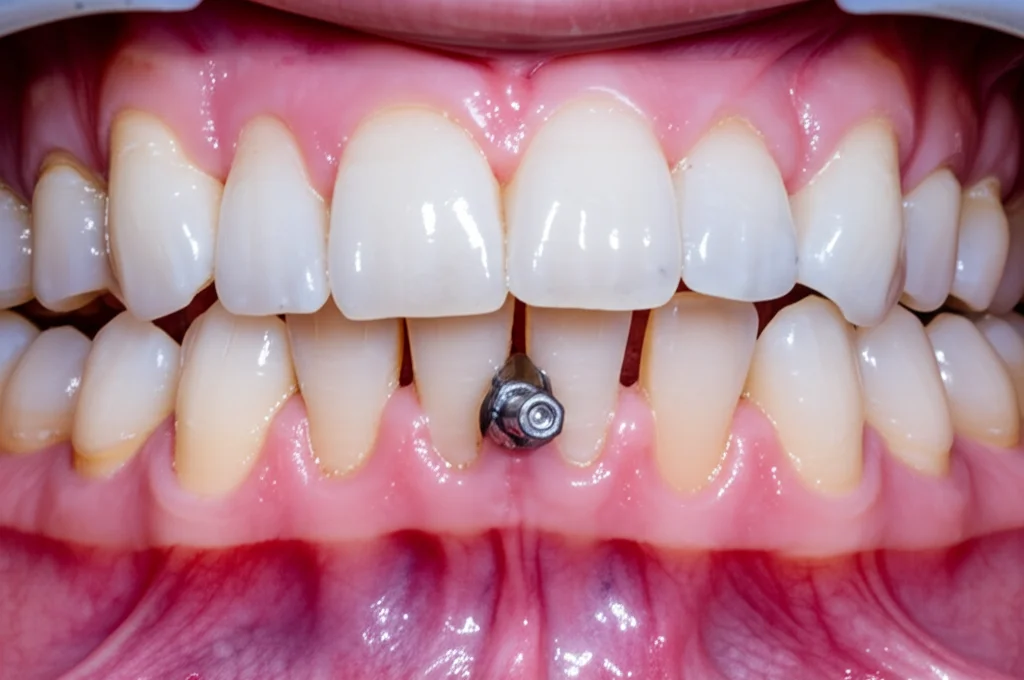

Ma l’apparecchio da solo non bastava. Per realizzare i movimenti complessi necessari – spostare indietro (distalizzare) tutta l’arcata superiore e la parte destra dell’arcata inferiore, e contemporaneamente spostare avanti (mesializzare) la parte sinistra dell’arcata inferiore – avevamo bisogno di un ancoraggio solidissimo. Ecco che entrano in scena le miniviti ortodontiche (o miniscrew). Ne abbiamo inserite strategicamente: due nel palato, tra i molari superiori, una sulla mandibola a destra (nella cosiddetta “buccal shelf”) e una tra canino e secondo premolare inferiore a sinistra. Queste piccole viti in titanio, inserite nell’osso con una procedura minimamente invasiva, fungono da punti di ancoraggio fissi, permettendoci di applicare forze precise senza effetti collaterali indesiderati sugli altri denti.

Il trattamento è iniziato con l’applicazione dell’apparecchio linguale, realizzato su misura grazie a mascherine di trasferimento stampate in 3D. Abbiamo usato una sequenza di archi ortodontici sempre più rigidi per allineare e livellare i denti. Dopo circa un mese, sono stati estratti i denti del giudizio. Dopo cinque mesi, siamo passati ad archi in acciaio rettangolari e abbiamo inserito le miniviti.

A questo punto è iniziata la fase “clou”: abbiamo applicato forze (tramite elastici o molle collegate alle miniviti) per distalizzare l’arcata superiore e il quadrante inferiore destro, e contemporaneamente per mesializzare il quadrante inferiore sinistro. Sul lato sinistro, abbiamo usato anche elastici intermascellari di Classe II per aiutare la correzione.

Ci sono voluti circa 10 mesi di questa meccanica complessa per chiudere gli spazi e correggere le discrepanze antero-posteriori. La paziente era già molto contenta vedendo i suoi incisivi rientrare e le labbra meno sporgenti! L’ultima fase, detta di “finishing”, è servita a perfezionare l’allineamento e l’ingranaggio tra i denti, usando anche piccoli bottoni estetici sulla superficie esterna dei denti posteriori per applicare elastici verticali e cross-bite (per correggere eventuali leggere discrepanze trasversali dovute ai movimenti).